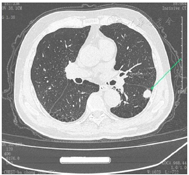

2021年12月7日第1次入院全麻下行胸腔镜下左下肺背段切除+淋巴结清扫+粘连烙断+左上肺大疱切除肺修补术。术后病理结果示:1.(左下叶)肺低分化癌伴坏死,待免疫组化进一步检测,肿块大小1.8 cm×1.5 cm×1.5 cm;局部侵犯脏层胸膜,脉管内见癌栓,支气管及神经未见肿瘤侵犯,肿块旁见气道播散;间质淋巴细胞反应(少量);另见钙化血吸虫卵沉着。2.(手术切缘)阴性。3.(左上)肺大疱。4.(第7组)1枚、(第10组)4枚、(第11组)2枚淋巴结呈慢性炎,均未见癌转移。5.免疫组化(I2021-00862B)示,CK5/6(−)、CK7[弱(+)]、TTF-1(+)、P63(−)、P40(−)、EGFR(−)、ALK(−)、Ki-67(+)60%、GATA3(−)、CD56(+)、CgA(+)、Syn[弱(+)]、CK20(−)、P16[弱(+)]部分、PD-1(+)10%、PD-L1(−)肿瘤细胞。补充报告示(左下叶)肺低分化癌伴坏死,结合免疫组化,符合肺小细胞癌伴坏死,见图1。胸部CT平扫+靶重建结果见图2。

如图2所示,患者左肺下叶背段结节影恶性待排,建议增强CT检查。右肺上叶、左肺下叶实性结节。肺气肿,肺大疱。两肺散在纤维灶,冠脉条状致密影。